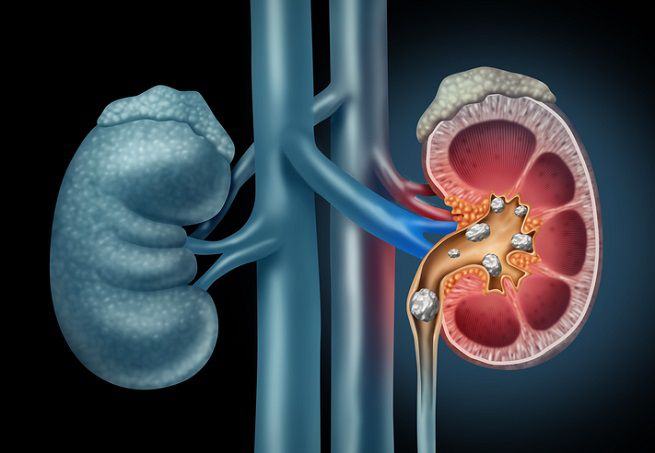

In tanti credono che l’acqua del rubinetto faccia venire i calcoli renali perché la considerano più impura.